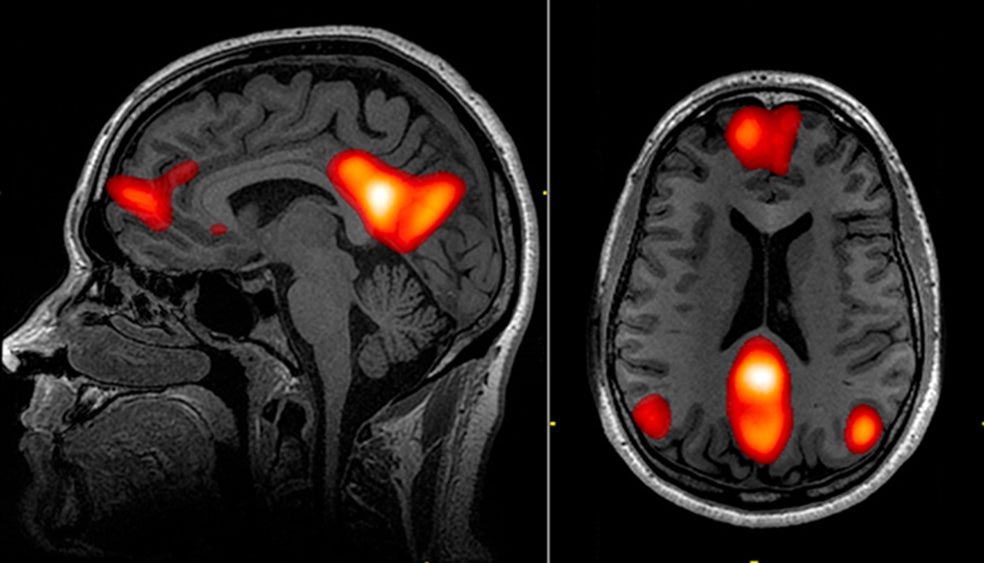

Así se ve la mente que vagabundea. La red neuronal por defecto es el conjunto de regiones del cerebro que se activan cuando el cerebro está en reposo o divaga. Antes de la tecnología RMf, que permite detectar este tipo de actividad, se creía que la actividad del cerebro disminuía radicalmente cuando se producía ese proceso. Ahora se sabe que se trata tanto de un 'ahorro energético' como de una conexión neuronal distinta.

La responsable de este 'efecto ducha', en términos fisiológicos, es la red neuronal por defecto, una función de nuestro cerebro que se activa cuando entramos en modo 'desconexión'. Las resonancias magnéticas funcionales han permitido en los últimos años visualizar cómo la actividad de esta red se desarrolla en los lóbulos temporal, parietal y prefrontal.  Cuando desconectamos o dejamos vagar nuestra mente, esa red se activa como una onda que fluctúa cada ciertos milisegundos. El cerebro relajado, por ponerlo en palabras sencillas, no se 'apaga' sino que se mueve en otra 'longitud de onda'.